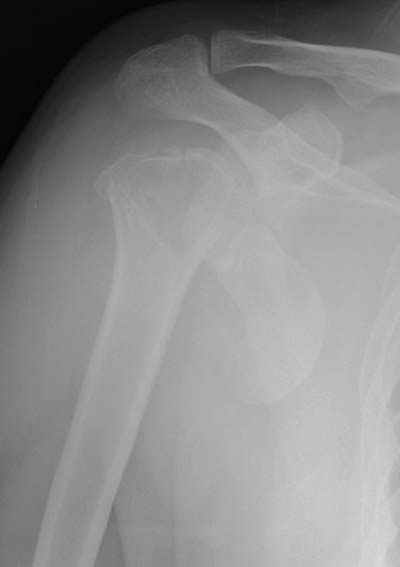

Здесь случай перелома-вывиха плеча, больному 56 лет, после "дважды" закрытой неудачной репозиции, опять же ургентно взяли в операционную, после полного общего обезболивания попытались сделать репозицию, и фиксацию провели спицами.

Больной амбулаторный, предупрежден на случай осложнения АВН головки.